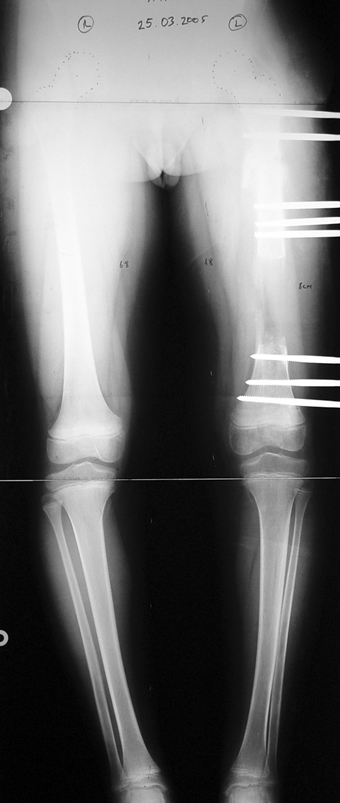

Appropriate radical debridement necessitates excision of all necrotic bone and soft tissues, and frequently causes instability at the involved extremity. The remaining bone and soft tissue defect has to be fixed and reconstructed. The distraction osteogenesis method of Ilizarov is used successfully for achievement of union, correction of the deformity, elimination of limb length inequality and reconstruction of segmental bone defects.

The duration of external fixation (external fixation index) depends on the amount of distraction required, and the extremity is prone to complications during this period. After the distraction phase is completed, the external fixator remains in place during the consolidation phase, which lasts twice as long as the distraction phase; but this period is hardly tolerated. If the external fixator is removed before sufficient consolidation is achieved, fractures, deformity and shortness will be the result. In our department, ‘lenghthening over nail’ method is used in order to decrease the external fixation index and increase patient comfort and activity level. In this method, the intramedullary nail is statically locked after the completion of the distraction phase, and external fixator is removed. The extremity is stabilized by the intramedullary nail during consolidation phase. In this way, complications due to long external fixation index or early removal of the external fixator are avoided.